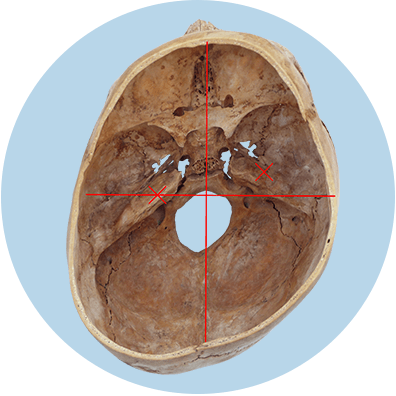

Als Definition für Plagiocephalus findet sich die Beschreibung als asymmetrisch abgeflachter Hinterkopf beim Säugling. Hierbei ist vor allem der hintere Schädelknochen, der Os occipitalis, betroffen. Dabei handelt es sich um eine posteriore Plagiozephalie. Diese kann sowohl rechts als auch links stattfinden. Sie ist möglich, weil zwischen den Schädelknochen sog. Gewebenähte oder Knorpelfugen (Sutura) bestehen, die indirekt wie Gelenke funktionieren.

Es gibt zusätzlich die sog. Einteilung nach Argenta. Der amerikanische Mediziner Louis Argenta hat die occipitale, posteriore Plagiozephalie bei Säuglingen in fünf Typen klassifiziert. So spricht man beispielsweise von Argenta Typ 2, wenn sich die Ohrachse verschoben hat (sog. ear-shift), oder von Argenta Typ 3, wenn sich zusätzlich die Stirn vorwölbt.

Durch die Verschiebung der Ohrachse (ear shift) wird der Gleichgewichtssinn beeinträchtigt. Das erschwert den Kleinkindern die motorische Entwicklung. Zusätzlich kann die Belüftung des Mittelohres durch die Eustachische Röhre eingeschränkt sein und sogar der Gehörgang verengt werden, was beides das Hörvermögen vermindern kann. Im Falle, dass das Kind später eine Brille braucht, kann die Anpassung sehr aufwändig werden, wenn der Nase-Ohr-Abstand auf beiden Seiten unterschiedlich ausfällt.

Die Verformung des Schädels schließt auch die Schädelbasis mit ein und da auch die Halswirbel noch verformbar sind, können sich diese nun ebenfalls asymmetrisch zueinander verschieben. Hierbei kommt es nun zu einer reduzierten Kopf- und Wirbelsäulenmobilität. Das Ganze kann durch eine Vorzugshaltung hin zu einer Lieblingsseite des Säuglings nochmals verstärkt werden. Wenn sich die Kinder dann zum Sitzen und Stehen aufrichten, wird häufig der Kopf schief gehalten – was zu einer skoliotischen Fehlhaltung führen kann. Die Muskeln werden einseitig stärker beansprucht und verspannen deutlicher, was sich in Schulter-, Nacken- und Kopfschmerzen ausdrückt. Inwiefern das auf die Nervenbahnen drückt und Auswirkungen auf die Verdauung hat, kann nicht abschließend beantwortet werden. Wird dies jedoch nicht behandelt, kann die gesamte Körperwahrnehmung gestört werden, was sogar noch bei Erwachsenen ausgeprägt ist. Langfristig kann das ebenfalls zu weiteren Rumpfasymmetrien führen.